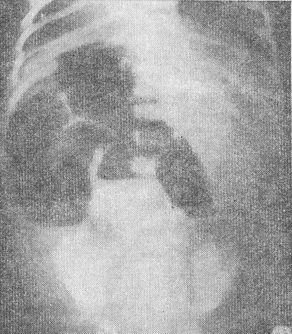

![]() 12. Рентгенограма новонародженого з тонкокишковій непрохідністю (пояснення в тексті) |

Діагноз підтверджують при рентгенологічному обстеженні. Крім оглядової рентгенографії, виробленої у вертикальному положенні новонародженого (прямий і правій бічній проекціях), при якій виявляють рівні рідини в розширених петлях тонкої кишки і арки (рис. 12), виробляють ірігографію з барієвою суспензією або йодолиполом. Ірігографію з контрастним речовиною корисно проводити тільки в тому випадку, якщо у дитини не відходив меконій. Якщо меконій, навіть у невеликій кількості, відходив, іригографія малоцелесообразна. У разі атрезії клубової кишки при ирригографии знаходять звужену товсту кишку і розширені петлі тонкої кишки (позитивний симптом «тонкої» товстої кишки). Цей симптом є абсолютним підтвердженням повної кишкової непрохідності. При підозрі на низьку тонкокишкову непрохідність не призначають контрастного рентгенологічного дослідження через рот, так як це подовжує терміни діагностики вад розвитку.